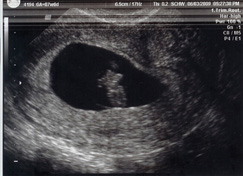

Sonograms

amfm714

12/28/09

7wk 6dy